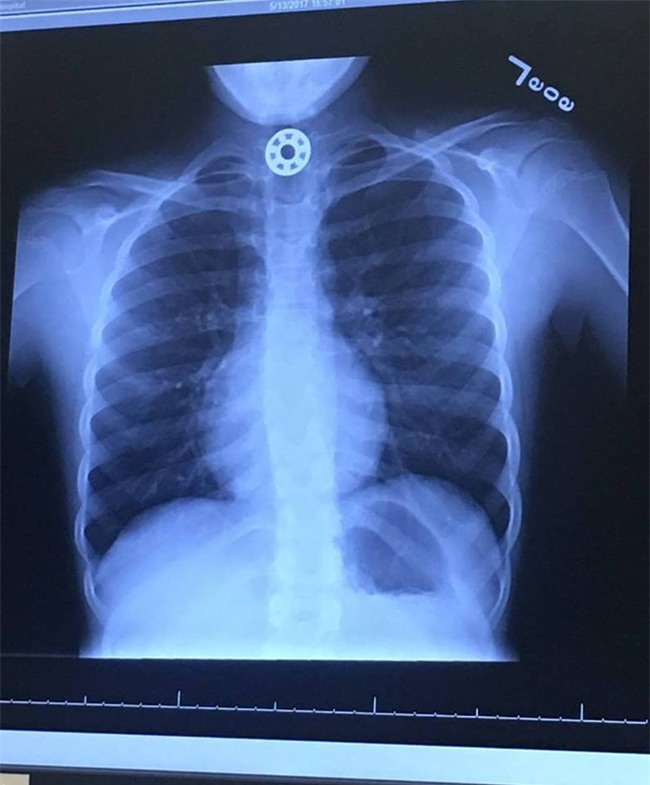

Lập tức Kelly đã đưa con gái đi cấp cứu. Các bác sĩ tại Bệnh viện Nhi Texas đã phát hiện ra miếng kim loại mắc kẹt trong thực quản của Britton sau khi chụp x-quang. Để lấy được dị vật ra, các bác sĩ phải gây tê Britton và tiến hành mổ nội soi.

(Ảnh: thefeels)